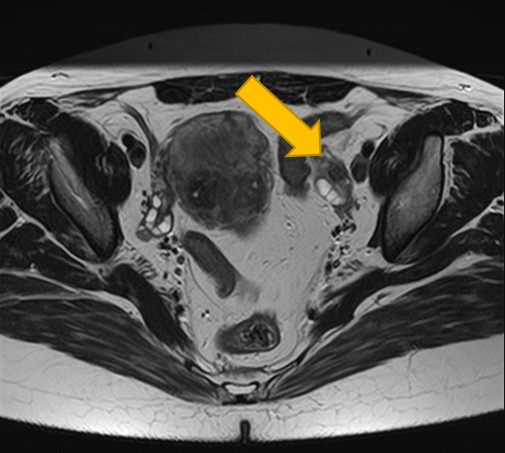

2. 卵巣腫瘍(嚢腫)のMRI:良性・悪性を判断する「中身」と「充実部分」の評価

卵巣嚢腫の中身が液体、脂肪、血液など何であるか、嚢腫壁の性状(肥厚、隔壁の有無)、充実部分の有無や血流を評価することで、良性か悪性(がん)かの可能性を判断する重要な手がかりとなります。

| 卵巣嚢腫 | 嚢腫の中身(液体・脂肪・血液など)、壁の厚さ、隔壁や充実部分の有無、内部の血流評価による良悪性の可能性。 |